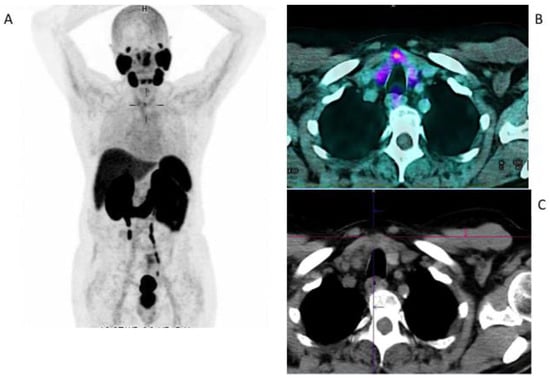

- De Vries, L.H.; Lodewijk, L.; Braat, A.J.; Krijger, G.C.; Valk, G.D.; Lam, M.G.; Rinkes, I.H.; Vriens, M.R.; de Keizer, B. 68 Ga-PSMA PET/CT in radioactive iodine-refractory differentiated thyroid cancer and first treatment results with 177 Lu-PSMA-617. EJNMMI Res. 2020, 10, 18. [Google Scholar] [CrossRef] [PubMed]

- Lawhn-Heath, C.; Yom, S.S.; Liu, C.; Villanueva-Meyer, J.E.; Aslam, M.; Smith, R.; Narwal, M.; Juarez, R.; Behr, S.C.; Pampaloni, M.H.; et al. Gallium-68 prostate-specific membrane antigen ([68 Ga] Ga-PSMA-11) PET for imaging of thyroid cancer: A feasibility study. EJNMMI Res. 2020, 10, 128. [Google Scholar] [CrossRef] [PubMed]

- Verma, P.; Malhotra, G.; Agrawal, R.; Sonavane, S.; Meshram, V.; Asopa, R.V. Evidence of prostate-specific membrane antigen expression in metastatic differentiated thyroid cancer using 68Ga-PSMA-HBED-CC PET/CT. Clin. Nucl. Med. 2018, 43, e265–e268. [Google Scholar] [CrossRef] [PubMed]

- Pitalua-Cortes, Q.; García-Perez, F.O.; Vargas-Ahumada, J.; Gonzalez-Rueda, S.; Gomez-Argumosa, E.; Ignacio-Alvarez, E.; Soldevilla-Gallardo, I.; Torres-Agredo, L. Head-to-head comparison of 68Ga-PSMA-11 and 131I in the follow-up of well-differentiated metastatic thyroid cancer: A new potential theragnostic agent. Front. Endocrinol. 2021, 12, 794759. [Google Scholar] [CrossRef]